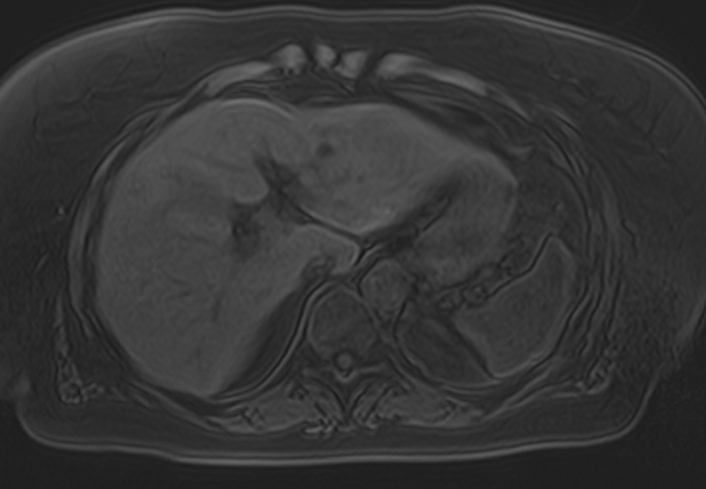

Магнитно-резонансная томография брюшной полости является наиболее информативной безопасной и эффективной методикой обследования внутренних органов. Метод позволяет проводить дифференциальную диагностику в сложных клинических случаях. Особенно это важно при противоречивых и неоднозначных данных, полученных при проведении УЗИ, рентгенографии, КТ или других обследованиях.

В клинике «Доступная медицина» МР томография проводится на новейшем высокопольном томографе экспертного класса TOSHIBA VANTAGE TITAN 1,5 Тесла. Высокая индукция магнитного поля обеспечивает повышенную четкость изображений при проведении обзорной МРТ брюшной полости, что гарантирует точность и эффективность диагностики заболеваний печени, желчного пузыря, поджелудочной железы и селезенки. Аппарат послойно сканирует исследуемую область с шагом от 1 мм в различных плоскостях, затем трансформирует результаты в трехмерные изображения превосходного качества. Для уточнения характера патологических изменений одного из органов назначается прицельная МР томография данного органа.